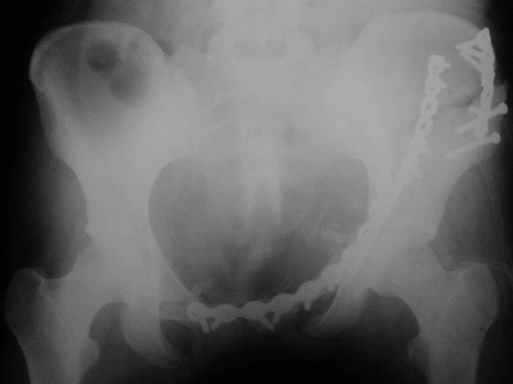

Рентгенограмма до операции

Перелом. Внутритазовый обзор.